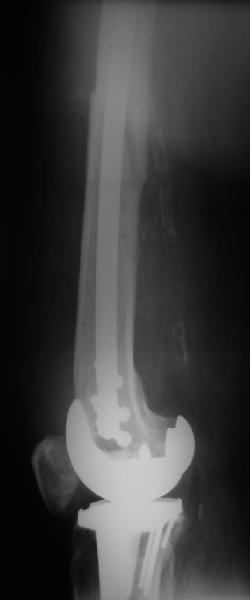

В приложении - недавний перипротезный перелом.

Методичка по закрытому интрамедулярному остеосинтезу при дистальных переломах бедра тут.

При низких переломах, когда клин опускается к суставу, пусть и без смещения внизу, мы опасаемся за стабильность когда есть шанс ввести дистальные блокировочные винты в клин.

Спасибо за ваш случай, очень элегантное решение перипротезного перелома.